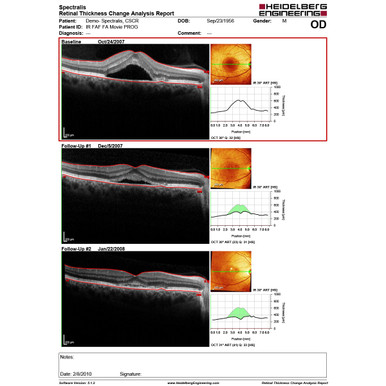

AutoRescan

Using the SPECTRALIS® fundus image like a map, the AutoRescan function automatically places follow-up scans in precisely the same position visit after visit. Accurate, automatic placement of follow-up scans is important for optimizing patient flow and for confident recognition of the small structural changes that are critical to the effective management of many ophthalmic conditions.

Studies have shown that SPECTRALIS with AutoRescan technology can reliably measure changes in retinal thickness as small as 1 micron.